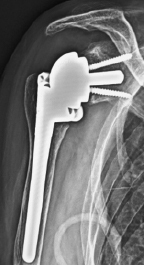

リバース型人工肩関節

肩腱板断裂

関節鏡下腱板修復術